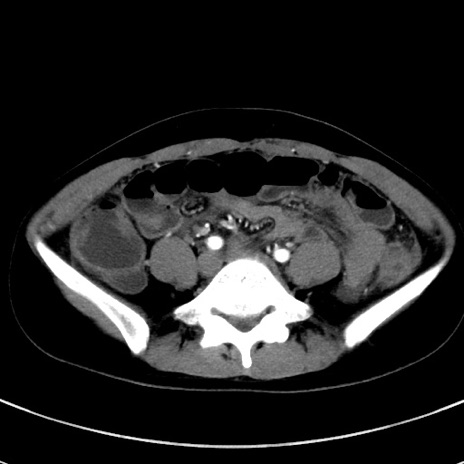

症例17(横断像)

【症例】20歳代女性

【主訴】嘔吐、下腹部痛

【現病歴】昨日夕食後に嘔吐し下腹部痛が出現。本日になっても嘔吐持続し改善しないため来院。

【身体所見】意識清明、BT 37.2℃、BP 108/67mmHg、腹部:平坦、やや硬、下腹部正中から右にかけて圧痛あり、反跳痛軽度あり、tapping pain(+)。

【データ】WBC 13600、CRP 14.94